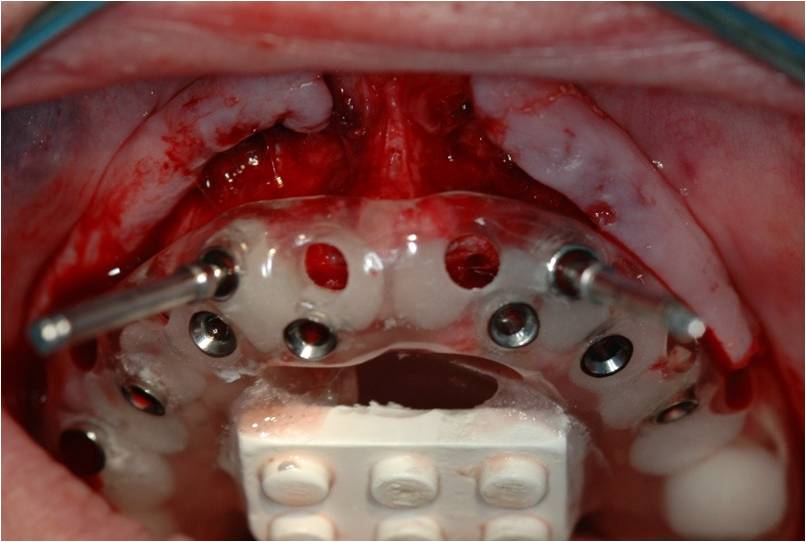

ההשתלות בוצעו דרך שבלונה שהוכנה במדפסת תלת מימד בהתאם לקובץ הממוחשב.

סוג השיקום הוא " קבוע נשלף" FIXED DETACHABLE.

זהו שיקום המתפקד כמו גשר קבוע יציב לחלוטין אך ניתן להסרה וניקוי בצורה יעילה כפי ששום שיקום אחר אינו מאפשר.